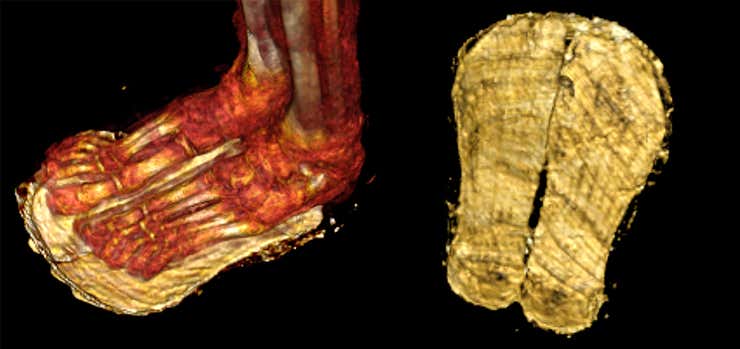

Las tomografías computarizadas también revelaron sandalias en los pies de la momia, probablemente hechas de papiro o fibras de palma. “Las sandalias probablemente estaban destinadas a permitir que el niño saliera del ataúd”, dijo Saleem en un comunicado hecho público en Frontiers. “Según los rituales descritos en el Libro de los Muertos de los antiguos egipcios , el difunto tenía que usar sandalias blancas para llegar piadoso y limpio al más allá”.